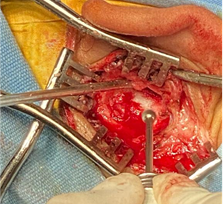

La paciente fue sometida a una biopsia incisional de la lesión, se extrajo un espécimen de 3 x 1.9 cm, a la visión macroscópica de superficie rugosa, de coloración blanca grisácea y de consistencia blanda; dicha muestra se envió al servicio de patología para su estudio, con un resultado de Linfoma No Hodgkin difuso de centro folicular de estirpe de células “B”. (Figura 5). Al igual se realizó inmunohistoquímica la cual reportó CD-3, CD-10, CD-20, BCL-2, BCL-6 Y Ki-67 positivos. (Figura 6 y 7).

|

|

(Figura 5) |